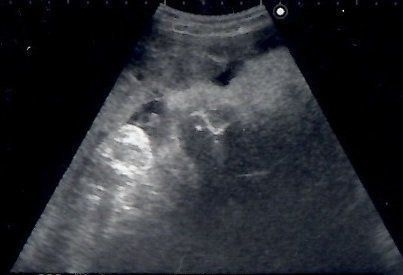

妊娠23週目のエコー写真 性別がほぼ確定

「性別は知りたいですか?」エコー画像を見ていた医師から問われて、「はい」と即答した私。しかし、告げられた性別は私が希望していたものではありませんでした。その日から数日間はかなり落ち込み、友人につい愚痴ってしまったほど。「赤ちゃんもおなかの中で聞いているよ。そんなこと言わないで」と友人からたしなめられ、ようやく我に帰りました。子どもを授かっただけでもうれしかった頃の気持ちを思い出して反省しました。